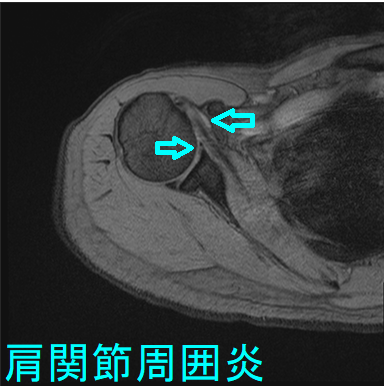

肩関節周囲炎とは肩・肩周囲の炎症で、中年に起こり易いため五十肩と呼ばれます。初期には肩関節を動かしても動かさなくても痛み、特に夜間の痛みが強くなります。数か月-数年で、肩関節を動かしにくくなり、服を着替えるにも困難が生じます。

五十肩は学術的な病名ではなく、国際的には癒着性関節包炎(adhesive capsulitis)や凍結肩(frozen shoulder)と呼ばれます。

肩関節周囲炎(癒着性関節包炎・凍結肩)は、糖尿病や甲状腺疾患との関連が強い[Am Fam Physician. 2008 Feb 15;77(4):453-60.]。

糖尿病の10%から20%に五十肩(肩関節周囲炎・凍結肩・癒着性関節包炎)が発病するとされますが、その原因は不明です。甲状腺ホルモンは、骨、軟骨、腱に影響するため、甲状腺機能低下症・甲状腺機能亢進症も、五十肩の発病に関連あるとされます。(J Biol Regul Homeost Agents. 2016 Jul-Sep;30(3):867-870.)(Arthritis Rheum. 1987 Aug;30(8):936-9.)

甲状腺機能低下症の重症度と、五十肩(肩関節周囲炎・凍結肩・癒着性関節包炎)の重症度に相関が認められます。(J Shoulder Elbow Surg. 2017 Jan;26(1):49-55.)

五十肩(肩関節周囲炎・凍結肩・癒着性関節包炎)自体の治療は、

- 抗炎症剤(NSAIDs)による鎮痛と消炎

- 肩関節が固まらないようにするための運動療法